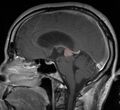

في كثير من الأحيان ، يُعرف شلل الحملقة إالعلوي جنبًا إلى جنب مع العديد من الموجودات العينية مثل رأرأة تراجع التقارب وتراجع الجفن المعروف أيضًا باسم علامة كولير وانفصال الضوء القريب (تتكيف الحدقة مع الضوء ولكنها لا تتفاعل مع الضوء) يسموا كمجموعة بمتلازمة بارينو[1] أو متلازمة الدماغ المتوسط الظهرية ، هي الأعراض الجسدية الوحيدة التي تظهر. يحدث هذا بسبب ضغط مركز الحملقة العمودي في سقف الدماغ المتوسط على مستوى الأكيمة العلوية والعصب القحفي III. يتضمن العمل عادةً التصوير العصبي كما يظهر على اليمين.[بحاجة لمصدر]